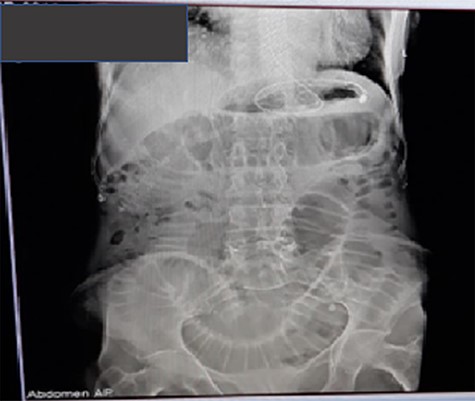

Sixty-five-year-old-female patient with known cardiac illness on follow-up for the last 10 years presented with crampy central abdominal pain associated with nausea, frequent bilious vomiting of 3 days duration. She has no previous experience of similar compliant and has no previous abdominal surgery. For the above compliant, she went to nearby clinic from where she was referred to Assela referral hospital for better evaluation and management. On arrival to emergency surgical department, she was emaciated, acutely sick looking with tachycardia of 110 beat/minutes and blood pressure of 130/75mmhg. Abdominal examination revealed distended, hypertympanic abdomen with hyperactive bowel sound, but there was no sign of peritoneal irritation. Hernial sites were free, and digital rectal examination was unremarkable. Nasogastric tube insertion revealed bilious gastrointestinal content, and her basic laboratory examinations showed leukocytosis of 12,000 with left shift (neutrophil 85%), while plain abdominal X ray (Fig. 1) showed dilated small bowel loops with absent rectal gas shadow.

Plain abdominal X-ray showing dilated small bowel loops with visible valvulae conniventes.